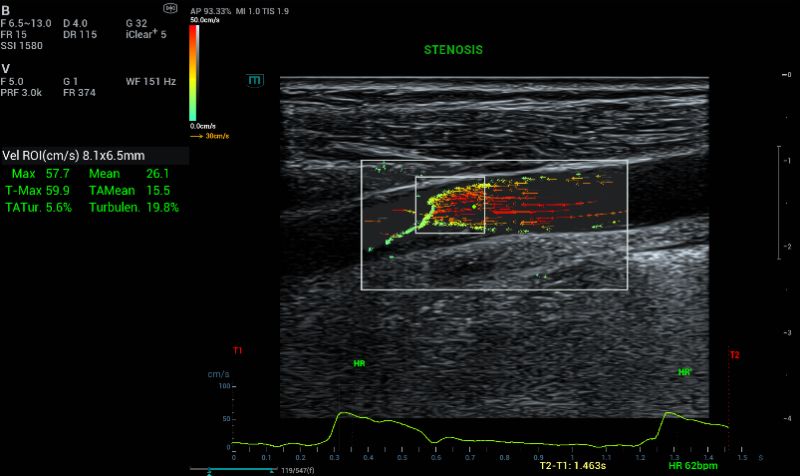

Color Doppler is a standard tool to assess stenosis and overall flow. CF shown reversal flow at the stenosed area (Fig 2).

B mode and CF images of the right carotid plaque.

Fig.1 and 2: B mode and CF images of the right carotid plaque.